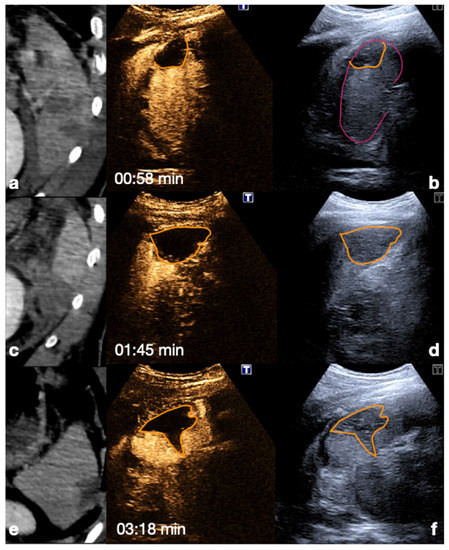

Figure 10.

CT (a,d) and follow-up CEUS (b,c,e,f) of the right kidney in a 57−year-old patient who fell from a height. Follow-up CEUS was performed four days after the admission CT. Note at CEUS the progressive enhancement, at different time points, of the renal cortex in about 30 s (b,c) and the medulla, up to 2.5 min (e,f). The parenchymal hematomas appear as non-enhancing collections (b,e, orange lines) contained in the organ capsule (b, pink lines), without internal enhancing vessel or associated vascular injuries. Due to the physiological evolution of the hematoma, the follow-up, it shows small fluid anechoic areas related to the progressive resorption (e, arrow). Adopted from ref. [30], 2021, Iacobellis, F.; et al.

Figure 11.

Adrenal gland hematoma. CEUS (a) and contrast-enhanced CT (b) of a 44−year-old male patient after a motor vehicle accident, showing right adrenal gland hematoma with no vascular complication. CEUS (c) and contrast-enhanced CT (d) follow up of a 36-year-old male patient on day 3 after a car accident; a pseudo-aneurysm within the right adrenal gland hematoma is visible (white arrows).